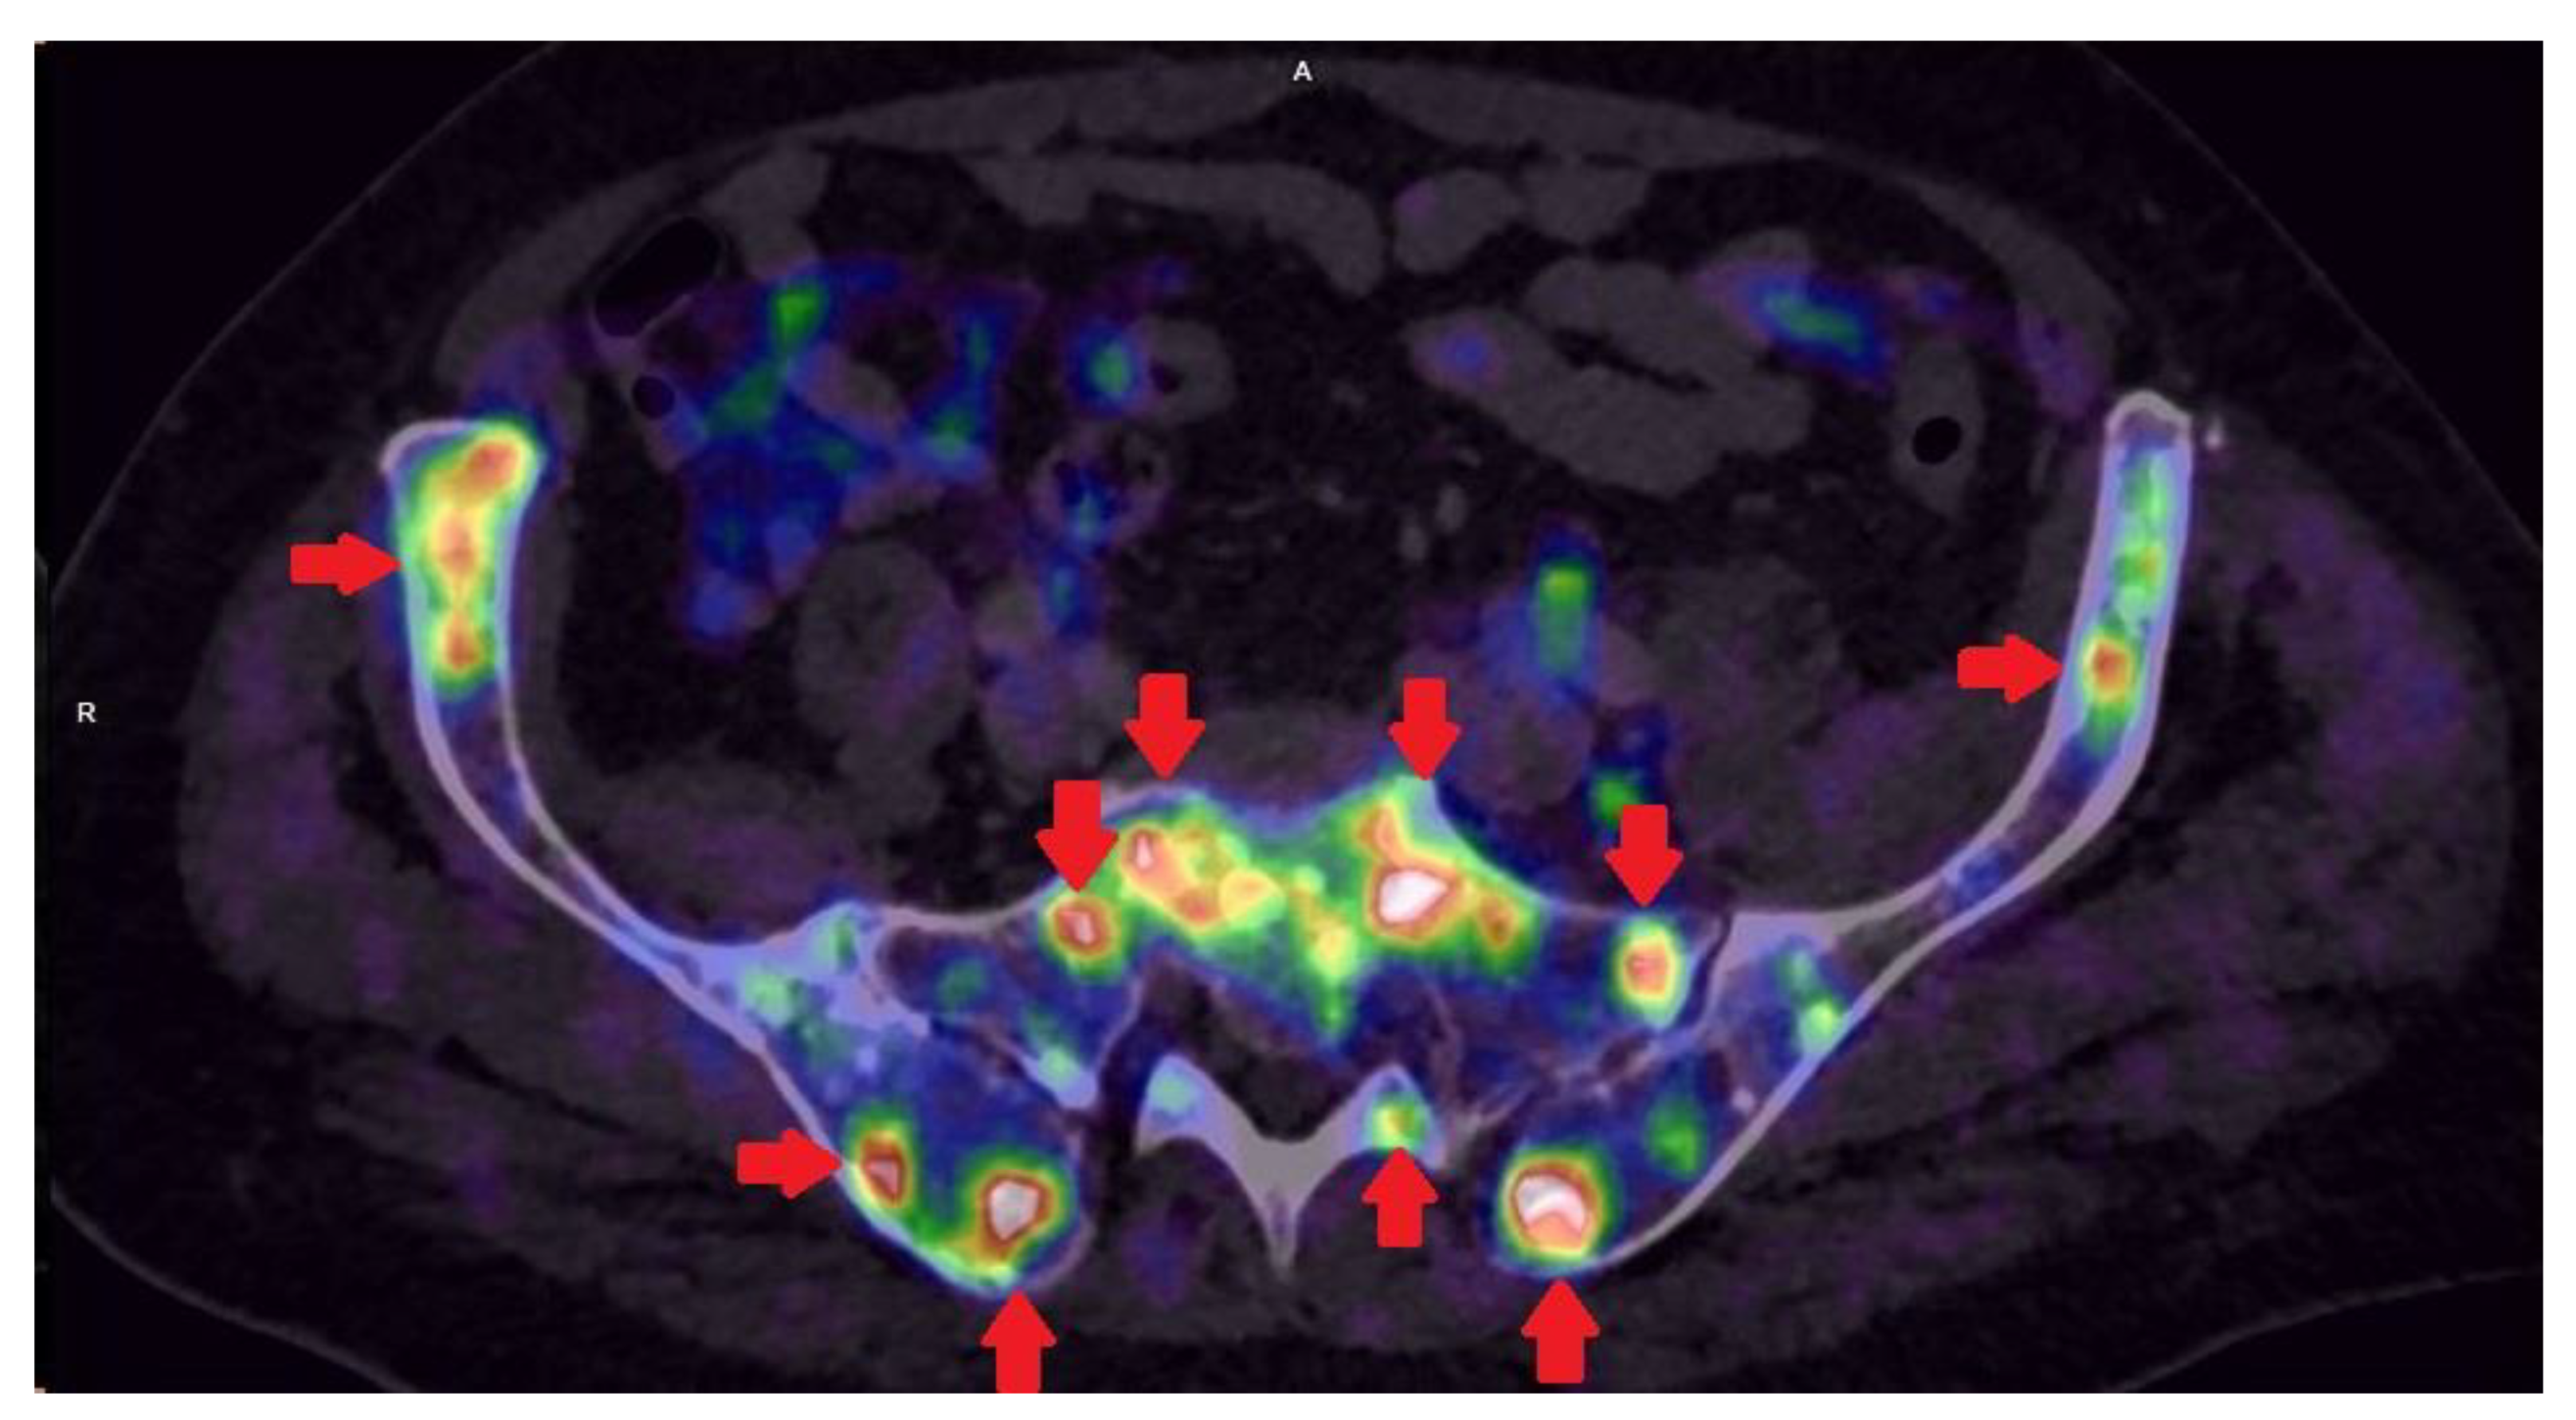

2.4. The Key Role of Imaging Techniques in Staging and Surgical Navigation